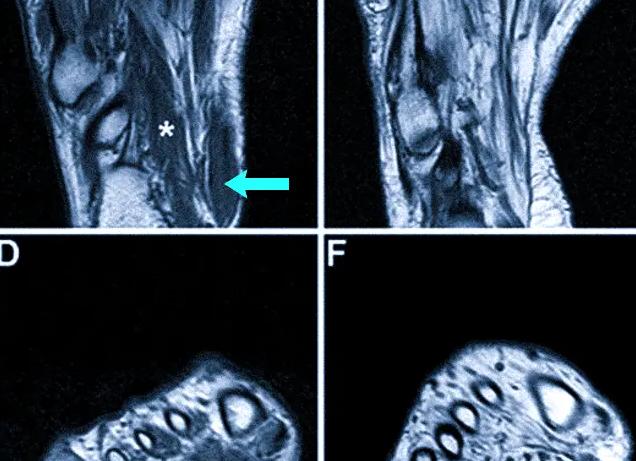

После исследования врач проводит скрупулезное изучение полученных результатов. Он располагает снимками в трех плоскостях: фронтальной (вид спереди), горизонтальной и сагиттальной (вид сбоку).

На трехмерной модели становятся явными:

- Травмы (разрыв сухожилия или связок, внутрисуставные переломы, кровоизлияния, ушибы костей пятки).

- Импиджмент-синдром – защемление мягких тканей между двумя костями. Снимок МРТ позволяет выявить опухоли, разрывы мягких тканей или кровоизлияния внутри сустава

- Артрозы и артриты с различной степенью разрушения и деформации костных и хрящевых структур, отложением солей и внутрисуставным выпотом.

- Опухоли с определением их границ.

- Склеротические посттравматические изменения.

- Состояние тканей после операции на суставе или стопе.